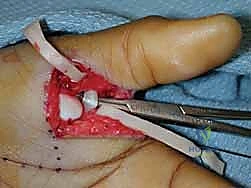

العلاج الجراحي: الدقة والاحترافية مع أ.د. محمد هطيف

عندما تفشل العلاجات التحفظية، أو في حالات التمزق الكامل (الدرجة الثالثة)، الكسور الانقلاعية الكبيرة، عدم الاستقرار المزمن، أو وجود "آفة ستينر"، يصبح التدخل الجراحي الخيار الوحيد لإنقاذ وظيفة اليد.

يُعد الأستاذ الدكتور محمد هطيف رائداً في جراحات اليد الدقيقة في اليمن. باستخدام تقنيات متقدمة مثل الجراحة الميكروسكوبية والتدخلات طفيفة التوغل، يتم تحقيق نسب نجاح تضاهي أفضل المراكز العالمية.